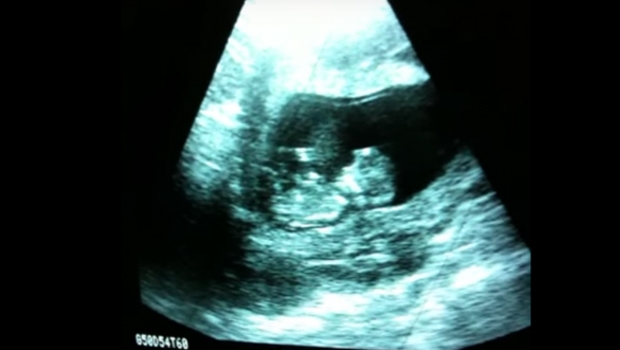

U ovom ćete ultrazvučnom snimku vidjeti kako beba radi gimnastiku u vodi.

Izvor: cafe.hr